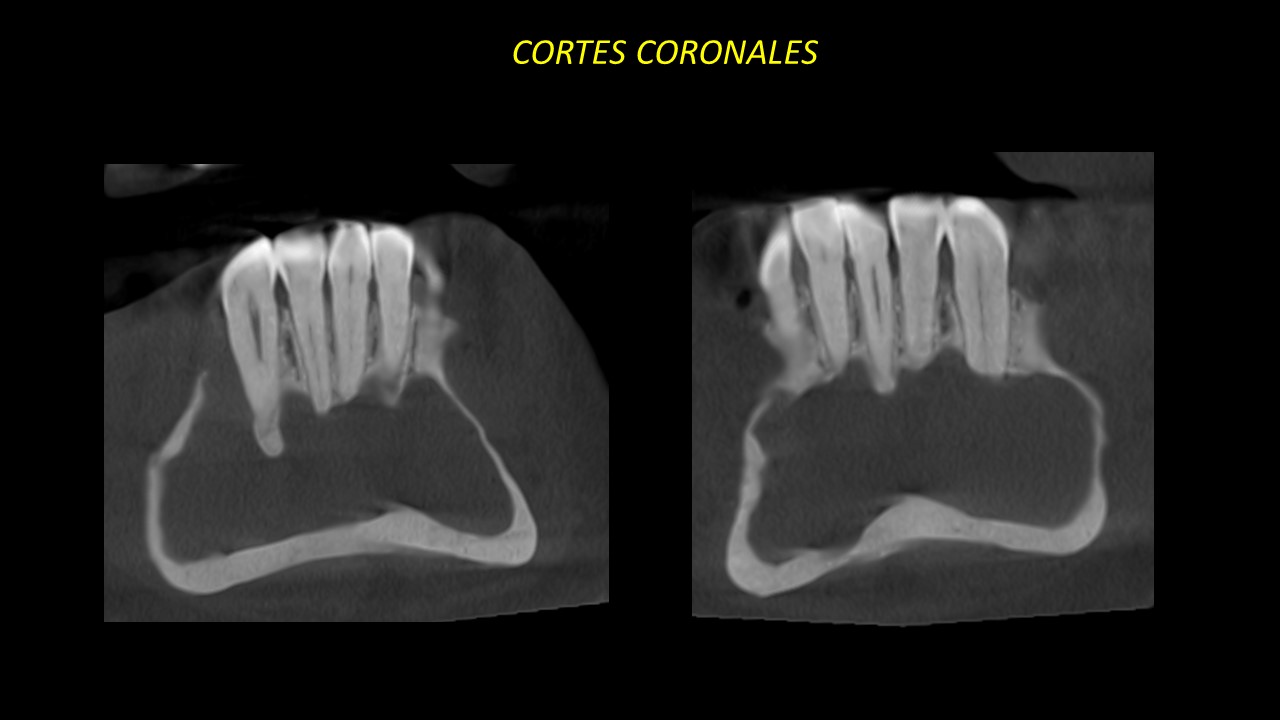

Figura 4

Figura 5

En los cortes coronales y sagitales podemos observar la pérdida de lámina dura a nivel apical de piezas 42,43 y 44. También se observa la reabsorción radicular externa de piezas 35,34,33,32 y 45 (Figuras 4 y 5).